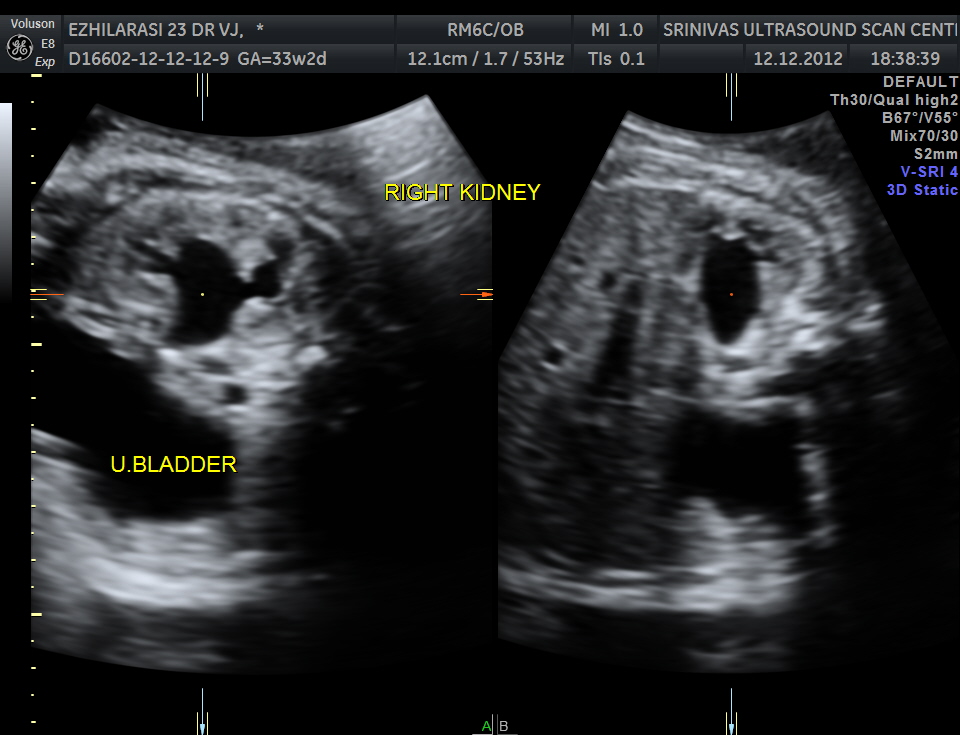

The fetus also showed bilateral pelvi calyectasis and rt ureteromegaly.